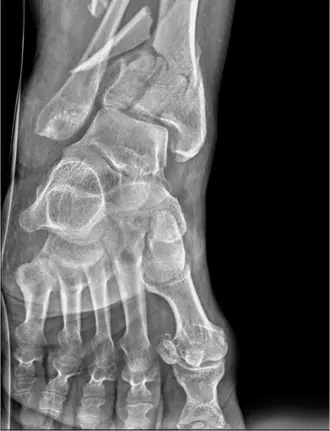

الأشعة السينية (X-rays)

هي أول خطوة في التصوير وتُجرى فورًا في قسم الطوارئ.

* اللقطات المطلوبة: تُؤخذ صور بالأشعة السينية من عدة زوايا (أمامية خلفية، جانبية، ولقطة الكاحل المائلة).

* ما تظهره الأشعة السينية:

* تُظهر كسرًا شديد التفتت ومزاحًا داخل المفصل في الجزء السفلي من عظم القصبة (كسر البيلون).

* تُظهر تضررًا كبيرًا في السطح المفصلي لسقف الكاحل.

* قد يظهر تفتت في الجزء العلوي من عظم القصبة (Metaphysis) وقصر في طول القصبة.

* غالبًا ما يُلاحظ كسر في الجزء السفلي من عظم الشظية أيضًا، مما يزيد من عدم استقرار المفصل.

* قد يظهر عظم الكاحل مزاحًا للأعلى، وهو ما يتوافق مع آلية الإصابة بالضغط المحوري.

صورة الأشعة السينية المبدئية لكسر بيلون معقد